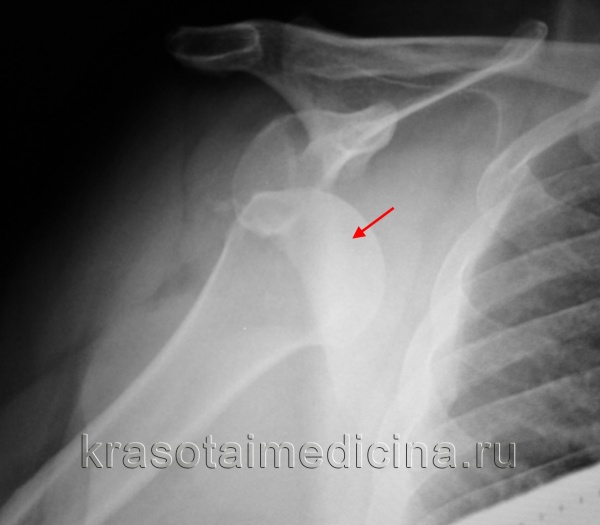

Рентгенография при вывихе плеча

Рентгенография плечевого сустава: вывих головки правой плечевой кости из суставной ямки.